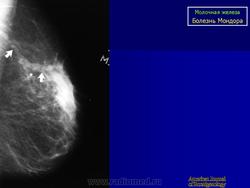

БОЛЕЗНЬ МОНДОРА

Тромбы могут образовываться в любых поверхностных венах. Флебит поверхностных вен переднебоковой поверхности грудной и брюшной стенок и области молочных желез называется болезнью Мондора. Французский хирург Мондор в 1939 году детально описал эту болезнь и впервые связал её с тромбофлебитом вен грудной и брюшной стенок.

При болезни Мондора у больных по ходу сосудов на грудной и брюшной стенке в области молочной железы возникают болезненные, шнуровидные утолщения, иногда протяженностью до 20 см.

Болезнь Мондора (Morbus Mondor)

Описана автором в 1939 г и известна также, как string phlebitis. Представляет собой воспалительный процесс, охватывающий v. thoracoepigastrica или v. thoracica lateralis, реже v. epygastrca superficialis по передне-боковой поверхности грудной клетки. В целом патогенез заболевания не выяснен. Некоторые авторы связывали возникновение данной формы тромбофлебита с mastitis vestigial. Существуют предположения об инфекционной и вирусной природе болезни Мондора, поскольку в ряде случаев отмечается увеличение регионарных лимфатических узлов. Встречается преимущественно у женщин среднего возраста, особенно с большими размерами молочной железы и иногда сопутствует неопластическому процессу в последней. В отдельных случаях пальпаторная характеристика тромбированной вены по своей твердости напоминает хорду, что дало основание для еще одного наименования: cord-like phlebitis. Температурная реакция чаще всего отсутствует. Рецидивы практически не наблюдаются. Морфологически обнаруживается облитерирующий эндофлебит.